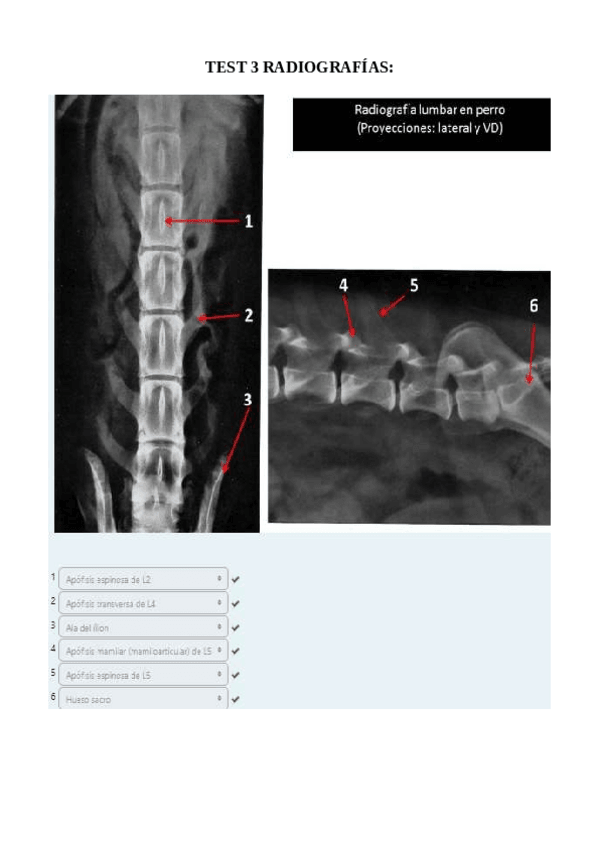

He publicado nuevos apuntes de 1º EMBRIOLOGÍA Y ANATOMÍA I: Radiografías práctica 6.pdf

8 páginas

He publicado nuevos apuntes de 1º EMBRIOLOGÍA Y ANATOMÍA I: SOLUCION-RADIOGRAFIAS-COMPLETAS.pdf

61 páginas

He publicado nuevos apuntes de 1º EMBRIOLOGÍA Y ANATOMÍA I: Todas-las-radiografias-de-anatomia-para-estudiar.pdf

129 páginas

He publicado nuevos apuntes de 1º EMBRIOLOGÍA Y ANATOMÍA I: TEST-3-radiografias-corregido.pdf

5 páginas